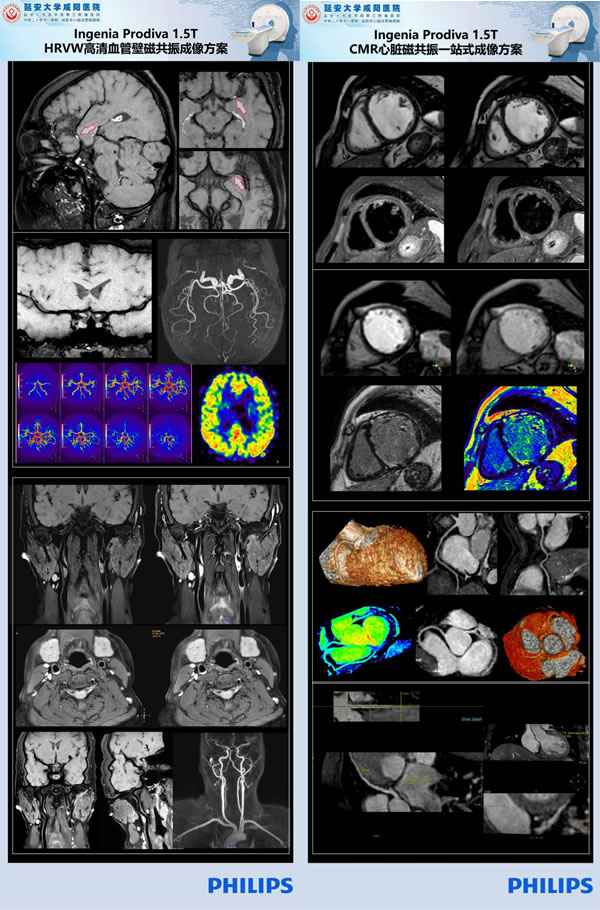

近十年來隨著磁共振成像技術的飛速發展,磁共振成像在心臟、大血管方面的應用價值越來越受到臨床的認可,甚至是依賴,心臟磁共振成像(Cardiac magnetic resonance imaging,CMRI)已經成為臨床心臟高端檢查之一。CMRI一次檢查即可以獲得心臟的解剖、功能、灌注、代謝及冠狀動脈分布等綜合信息,可以通過常規序列顯示心臟的大體形態;通過電影序列評估心肌功能;可以通過首過灌注及延遲強化診斷心肌疾病;并且磁共振還可以通過定量技術,反映組織特征,即所謂“一站式”心臟檢查。

延安大學咸陽醫院CT/MRI室在院長助理兼影像科主任劉連鋒教授帶領下,引進先進飛利浦1.5T Prodiva設備,通過不斷的學習研究,歸納總結,將高分辨磁共振血管壁成像這一項目由稚嫩發展至成熟的同時還在磁共振心臟、冠脈成像技術領域取得了重大突破,對掃描及診斷缺血/非缺血性心肌病、心包疾患、心臟瓣膜病及大血管病變等疾病篩查上邁出了關鍵性的一步!這項舉措不僅極大推動了1.5T磁共振心臟、冠脈成像技術在省內的開展,也是咸陽市三甲醫院開展此項目先例!